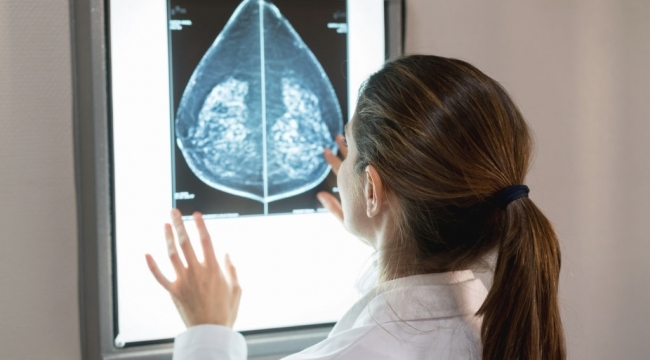

EGEOLAY/Uzmanlar büyük göğüslerin sırt, omuz ve boyun üzerinde ekstra baskı yarattığı ve tedavi edilmediği takdirde bu durumun fıtığa sebep olabileceği konusunda uyarıyor. Üniversite hastanesi olmasının ardından üçüncü basamak işlemlerin yapıldığı İEÜ Medical Park Hastanesi’nde, hastalar meme küçültme ameliyatı için SGK'dan destek alabilecek.

Meme küçültme ameliyatının estetik kaygıların yanı sıra medikal nedenlerden dolayı da yapıldığını söyleyen İzmir Ekonomi Üniversitesi Estetik Plastik ve Rekonstrüktif Cerrahi Doktor Öğretim Üyesi Op. Dr. Onur Evren Yılmaz, memelerin büyüklüğüne bağlı olarak görülen bel ve boyun ağrılarının meme küçültme ameliyatı ile çözülebilecek problemler olduğunu söyledi.

Meme küçültme ameliyatının memelerin normalden büyük ve sarkık olmasından dolayı ya da yol açtığı medikal problemlere bağlı olarak tercih edilen bir operasyon türü olduğunu söyleyen Yılmaz, “Büyük memeler omuz ve sırt ağrısına hatta fıtık hastalıklarının oluşmasına ve ilerlemesine sebep olabilir. Meme altında terleme, kızarma ve kaşıntı yapar. Sütyen askı yerinde çökmeye ve göğüs kafesine baskı yaparak akciğer kapasitesinin azalmasına neden olabilir. Meme küçültme ameliyatları oldukça sık yaptığımız ve hasta memnuniyeti yüksek işlemlerdir. Tüm bu fiziksel nedenlerin yanı sıra, memelerin büyüklüğünden rahatsız olan kişilere de yapılabilir. Meme küçültme ameliyatındaki amacımız, az ameliyat iziyle hastanın istediği boyutlarda, eşit büyüklükte, simetrik ve estetik görünüme sahip meme elde etmektir.” dedi.

Meme küçültme ameliyatının yaklaşık olarak 2 ila 3 saat arasında süren cerrahi bir işlem olduğunu belirten Yılmaz, “Ameliyatlarda ters T ya da lolipop kesi metotlarını kullanıyoruz. Ameliyatta hangi metodun uygulanacağına bir takım parametrelere bakarak karar veriyoruz. Bunlar kişinin gövde yapısına, memenin boyutuna, meme başının yerine, cilt yapısına göre değişiyor. Ameliyattan sonra hastamızı bir gün hastanemizde yatırıyoruz. Kendinden eriyen estetik dikişler olduğu için pansumana gerek olmuyor. 2 gün sonra yıkanmasına izin veriyoruz. Korkulduğu gibi ağrılı bir ameliyat değil. Sıklıkla duyduğumuz bir geri bildirim keşke daha önce olsaydım oluyor. Ameliyatın ardından birinci ve ikinci haftalarda kontrollerini yapıyoruz. İkinci haftada yapılan kontrol sonunda izlerin kaybolmasına yönelik kremler kullanıyoruz. Hastalar kısa sürede normal yaşamına geri dönüyor Genelde 5 gün sonra masa başı bir işe dönebilir hale gelinir. Daha doğum yapmamış ya da tekrar çocuk sahibi olmayı düşünen kişilerde emzirme ile ilgili çekinceler olabilmekte. Süt kanallarının korunarak yapıldığı yöntemlerle bu risk oldukça azalmaktadır. ” diye konuştu.

Sağlık açısından bu ameliyatı olması gerekli kişilerin 3. basamak bir hastaneden (üniversite ya da eğitim araştırma hastanesi) alınan heyet raporu ile sosyal güvence desteğinden faydalanabileceğinden bahseden Op. Dr. Onur Evren Yılmaz, “Kriterlere uyan uygun hastalarımız, İzmir Ekonomi Üniversitesi Medical Park Hastane’mizden meme küçültme ameliyatı için SGK desteğinden yararlanabilirler. Büyük memelerin fiziksel etkilerinin yanı sıra psikolojik olarak da olumsuz etkileri vardır. Kişide özgüven eksiliğine ve mutsuz olmasına neden olabilir. Bu şikâyetleri yaşayan kişilerin bu konuda deneyimli bir hekime başvurmaları gerekmektedir.” dedi.

Meme küçültme ameliyatının memelerin normalden büyük ve sarkık olmasından dolayı ya da yol açtığı medikal problemlere bağlı olarak tercih edilen bir operasyon türü olduğunu söyleyen Yılmaz, “Büyük memeler omuz ve sırt ağrısına hatta fıtık hastalıklarının oluşmasına ve ilerlemesine sebep olabilir. Meme altında terleme, kızarma ve kaşıntı yapar. Sütyen askı yerinde çökmeye ve göğüs kafesine baskı yaparak akciğer kapasitesinin azalmasına neden olabilir. Meme küçültme ameliyatları oldukça sık yaptığımız ve hasta memnuniyeti yüksek işlemlerdir. Tüm bu fiziksel nedenlerin yanı sıra, memelerin büyüklüğünden rahatsız olan kişilere de yapılabilir. Meme küçültme ameliyatındaki amacımız, az ameliyat iziyle hastanın istediği boyutlarda, eşit büyüklükte, simetrik ve estetik görünüme sahip meme elde etmektir.” dedi.

Meme küçültme ameliyatının yaklaşık olarak 2 ila 3 saat arasında süren cerrahi bir işlem olduğunu belirten Yılmaz, “Ameliyatlarda ters T ya da lolipop kesi metotlarını kullanıyoruz. Ameliyatta hangi metodun uygulanacağına bir takım parametrelere bakarak karar veriyoruz. Bunlar kişinin gövde yapısına, memenin boyutuna, meme başının yerine, cilt yapısına göre değişiyor. Ameliyattan sonra hastamızı bir gün hastanemizde yatırıyoruz. Kendinden eriyen estetik dikişler olduğu için pansumana gerek olmuyor. 2 gün sonra yıkanmasına izin veriyoruz. Korkulduğu gibi ağrılı bir ameliyat değil. Sıklıkla duyduğumuz bir geri bildirim keşke daha önce olsaydım oluyor. Ameliyatın ardından birinci ve ikinci haftalarda kontrollerini yapıyoruz. İkinci haftada yapılan kontrol sonunda izlerin kaybolmasına yönelik kremler kullanıyoruz. Hastalar kısa sürede normal yaşamına geri dönüyor Genelde 5 gün sonra masa başı bir işe dönebilir hale gelinir. Daha doğum yapmamış ya da tekrar çocuk sahibi olmayı düşünen kişilerde emzirme ile ilgili çekinceler olabilmekte. Süt kanallarının korunarak yapıldığı yöntemlerle bu risk oldukça azalmaktadır. ” diye konuştu.

Sağlık açısından bu ameliyatı olması gerekli kişilerin 3. basamak bir hastaneden (üniversite ya da eğitim araştırma hastanesi) alınan heyet raporu ile sosyal güvence desteğinden faydalanabileceğinden bahseden Op. Dr. Onur Evren Yılmaz, “Kriterlere uyan uygun hastalarımız, İzmir Ekonomi Üniversitesi Medical Park Hastane’mizden meme küçültme ameliyatı için SGK desteğinden yararlanabilirler. Büyük memelerin fiziksel etkilerinin yanı sıra psikolojik olarak da olumsuz etkileri vardır. Kişide özgüven eksiliğine ve mutsuz olmasına neden olabilir. Bu şikâyetleri yaşayan kişilerin bu konuda deneyimli bir hekime başvurmaları gerekmektedir.” dedi.